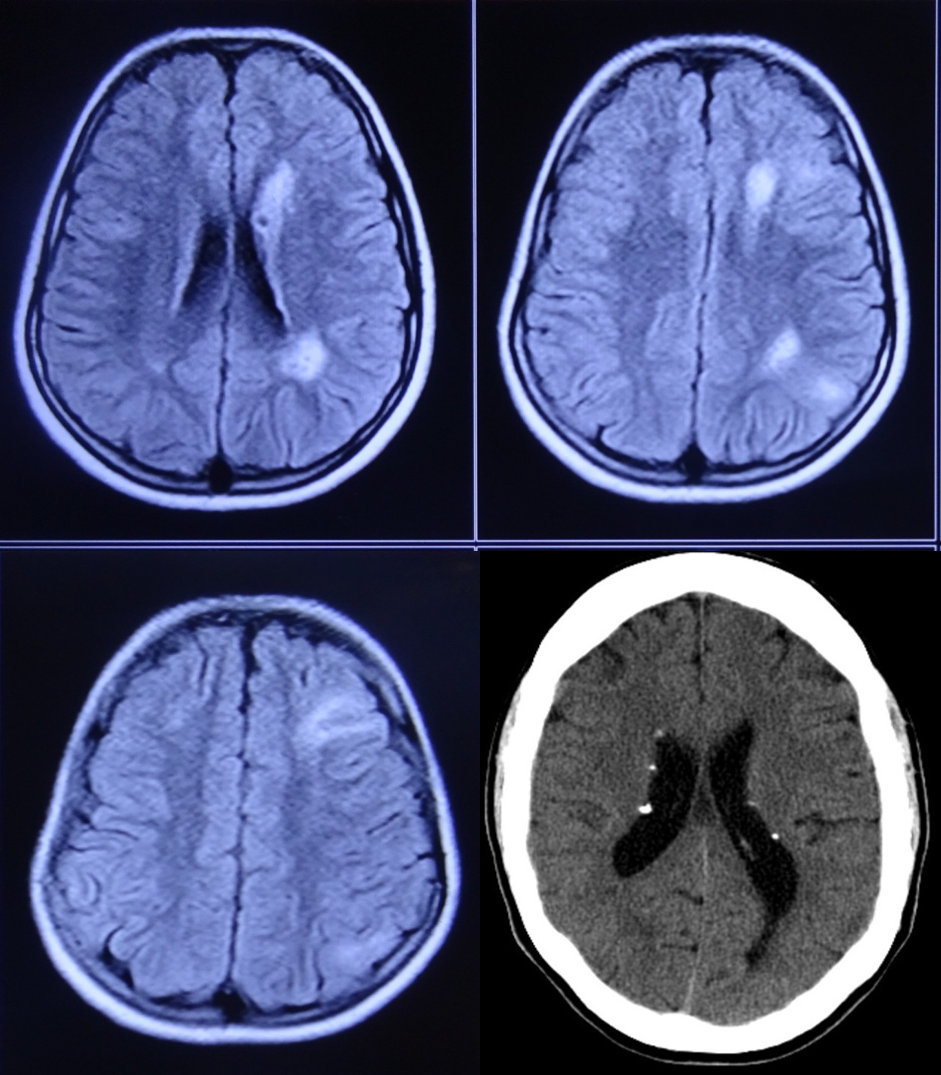

Question: A 36yrs lady with refractory epilepsy, failed multiple ASMs, shows following imaging findings.What are the further treatment options?

Explaination: Tuberous sclerosis:<br><br>Epilepsy occurs in 70% to 90% of patients, typically beginning in the first year of life<br>Refractory epilepsy is diagnosed in half of individuals with TSC and is predictive of development of intellectual disability<br>Introduction of an antiepileptic treatment during epileptogenesis and before the start of clinical seizures may prevent epilepsy onset and lead to a reduction in drug-resistant epilepsy<br>Everolimus proves as a add on treatment with response rate of 33% even at later age, without any age limit to individual benefit<br>Evaluation for epileptogenic tubers with FDG PET CT brain, if required SEEG for suspected lesions, followed by resectionThermoablation